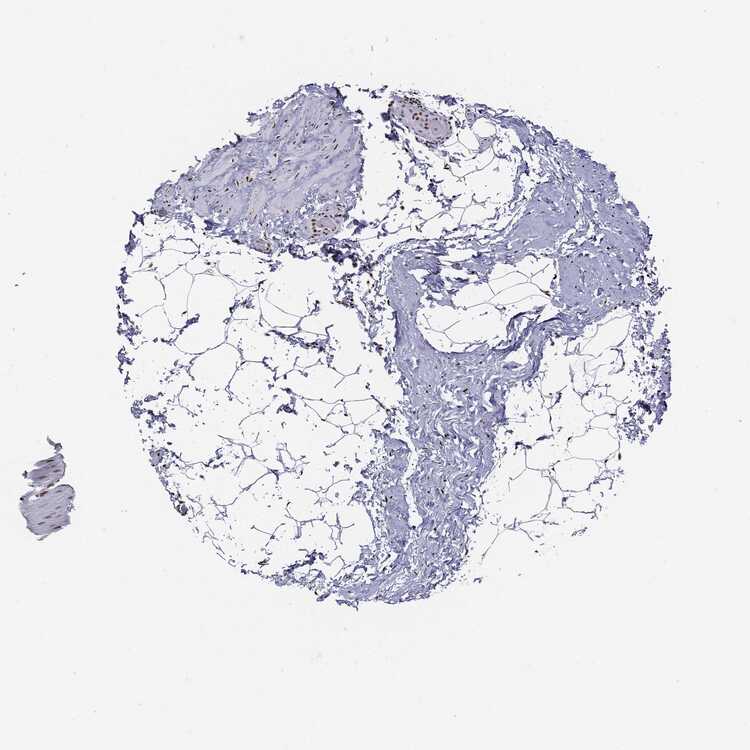

SOFT TISSUE 2 - Antibody stainingi

Antibody staining in the annotated cell types in the current human tissue is reported as not detected, low, medium, or high, based on conventional immunohistochemistry profiling in selected tissues. This score is based on the combination of the staining intensity and fraction of stained cells.

Each image is clickable and will lead to virtual microscopy that enables deeper exploration of all samples and also displays staining intensity scores, fraction scores and subcellular localization as well as patient and tissue information for each sample.

Antibody HPA030521Antibody HPA030522Antibody HPA030523Antibody CAB000148Antibody CAB080240Antibody CAB080241Antibody CAB080242

Chondrocytes LowMediumNot detectedNot detected---

Fibroblasts Not detectedMediumNot detectedNot detectedNot detectedNot detectedHigh

Peripheral nerve LowLowNot detectedNot detectedNot detectedHighHigh